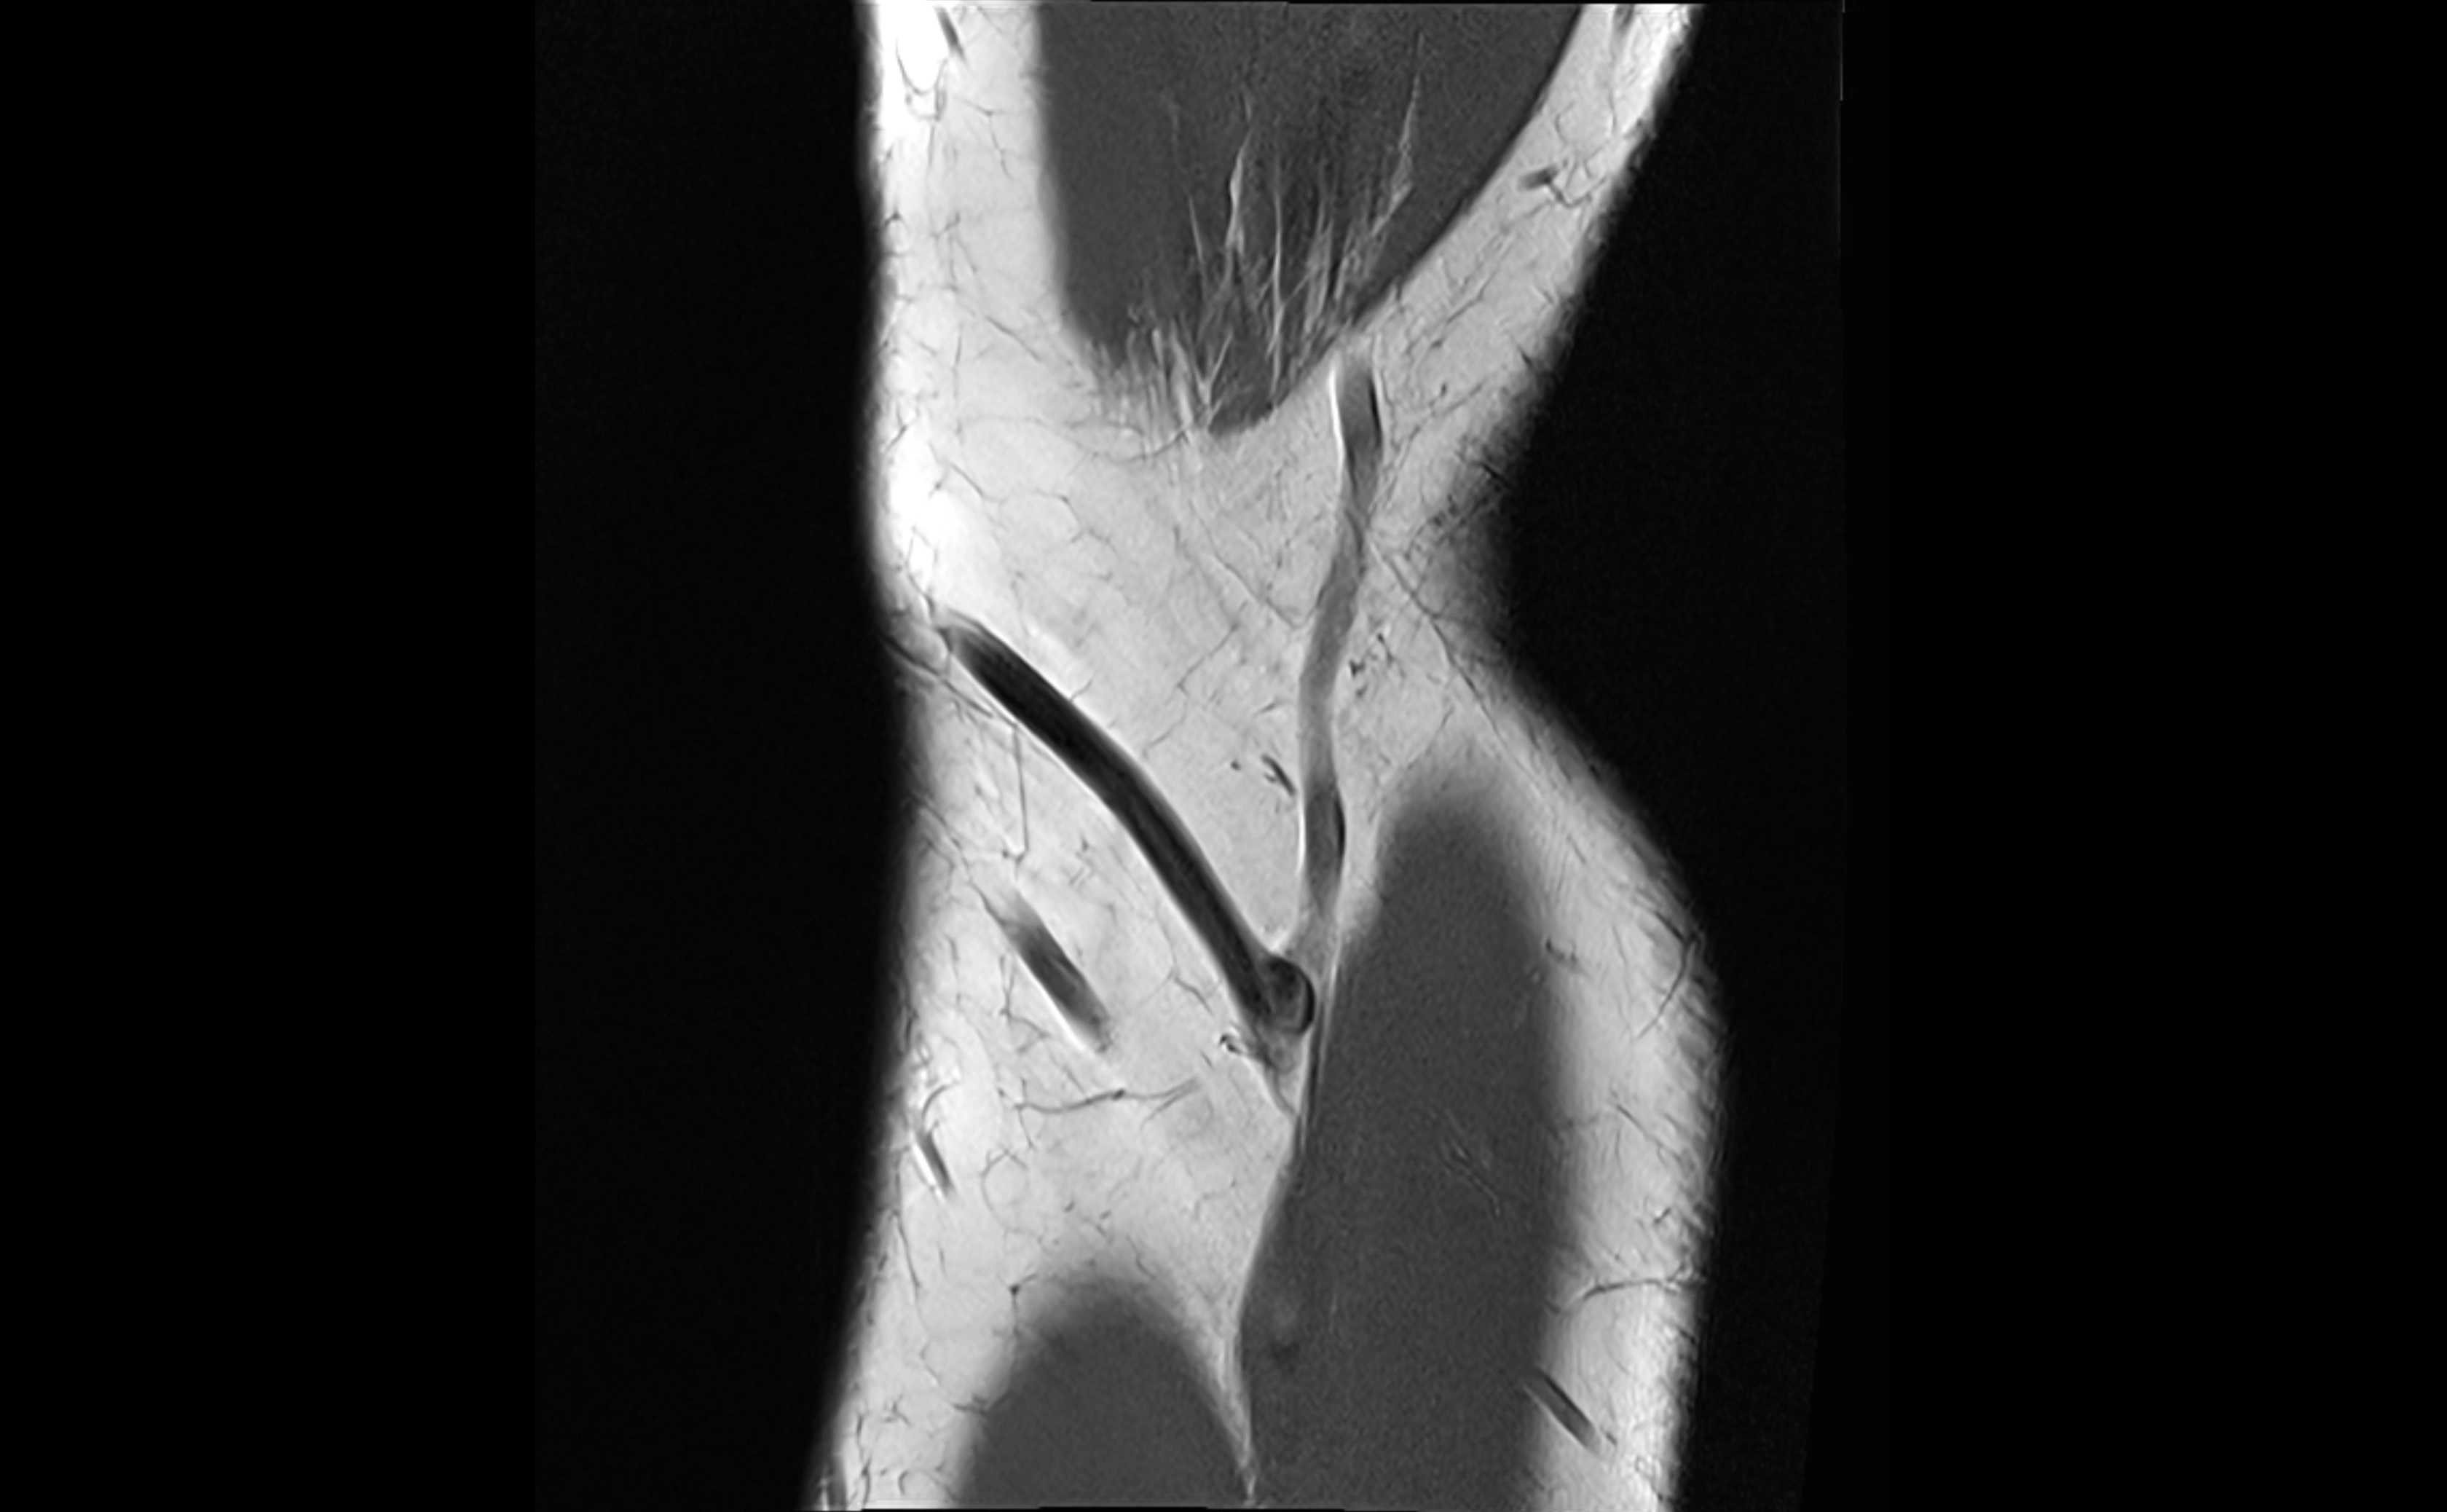

MRI Appearance

T1-weighted images:

• Ligament: low signal intensity (dark), appearing as a continuous band around the radial head.

• Adjacent fat and marrow: bright, creating contrast with the ligament.

• Thickening or disruption indicates injury or fibrosis.

• Joint capsule and synovium seen as thin low-signal lines contiguous with ligament margins.

T2-weighted images:

• Ligament: low signal (dark) with clear delineation from joint fluid.

• Fluid or edema: bright hyperintense, separating or surrounding the ligament in partial tears.

• Complete tear: discontinuity or non-visualization of ligament fibers, often with joint effusion.

STIR:

• Normal ligament: dark band encircling radial head.

• Pathology: bright hyperintense periligamentous signal suggesting edema, sprain, or partial tear.

Proton Density Fat-Saturated (PD FS):

• Normal: dark, well-defined band outlining the radial head.

• Partial tear: irregular or bright hyperintense signal within or adjacent to ligament fibers.

• Joint effusion and reactive synovitis appear bright and are well visualized.

MRI Arthrogram Appearance

• Contrast outlines the proximal radioulnar joint and radial head recess.

• Normal ligament appears as a dark ring surrounding the radial head, containing the injected contrast within the joint cavity.

• Partial tear: contrast extends along the ligament or beneath its fibers.

• Complete tear or subluxation: contrast extravasates around the radial head or ulna, indicating discontinuity.

• Detects capsular defects, instability, or synovial invagination with high sensitivity.